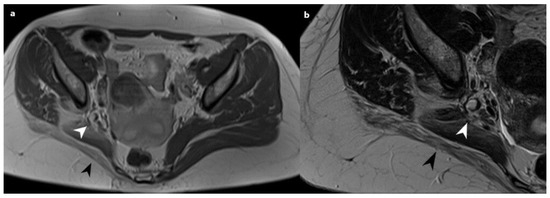

Immunohistochemically, the glands were positive for CK AE1/AE3 (DAKO, Agilent, Santa Clara, CA, USA, Monoclonal Mouse Anti-Human Cytokeratin Clones AE1/AE3-M3515, dilution 1:100, pH6), CK7 (DAKO, Agilent, Santa Clara, CA, USA, Monoclonal Mouse Anti-Human Cytokeratin 7, Clone OV-TL 12/30/M7018, dilution 1:100, pH9), and PAX8 (Cell Marque, Rocklin, CA, USA, Mouse Monoclonal Primary Antibody PAX8, Clone MRQ-50/06523927001, Ready-to-Use, pH8); stromal cells were positive for CD10 (DAKO, Agilent, Santa Clara, CA, USA, Monoclonal Mouse Anti-Human CD 10, Clone 56C6/IR648, Ready-to-Use, pH 9), WT1 (DAKO, Agilent, Santa Clara, CA, USA, Monoclonal Mouse Anti-Human Wilms Tumor 1 Protein, Clone 6F-H2/IR055, Ready-to-Use, pH9), and Vimentin (Novocastra, Leica Biosystems Newcastle, Newcastle, UK, Mouse Monoclonal Antibody Vimentin, Clone V9/NCL-L-VIM-V9, dilution 1:200, pH9); while estrogen (Novocastra, Leica Biosystems Newcastle, UK, Mouse Monoclonal Antibody Estrogen Receptor, Clone 6F11/NCL-L-ER-6F11, dilution 1:50, pH6) and progesterone receptors (Novocastra, Leica Biosystems Newcastle, UK, Mouse Monoclonal Antibody Progesterone Receptor, Clone 16/NCL-L-PGR-312, dilution 1:200, pH9) were positive in both stromal cells and glands. Based on the morphological and immunohistochemical characteristics, a diagnosis of endometriosis was made (Figure 2).

Figure 2. Pathology analyses: (ad): neural and perineural tissue infiltrated by endometrial types of glands and stroma; HEx40 (Mayer’s hematoxylin 05-06002/L, Bio Optica, Milano, Italy; Eosin Y 1% aqueous solution 05-10007/L, Bio Optica, Milano, Italy) (1–2) and HEx100 (3–4); (el): immunohistochemical features of the lesion: epithelial cells showed diffuse and intensive cytoplasmic CK AE1/AE3, CK7, and EMA positivity, as well as PAX8, estrogen, and progesterone nuclear positivity. On immunohistochemical analyses, stromal cells had membranous CD10 together with high nuclear WT1, estrogen, and progesterone positivity.